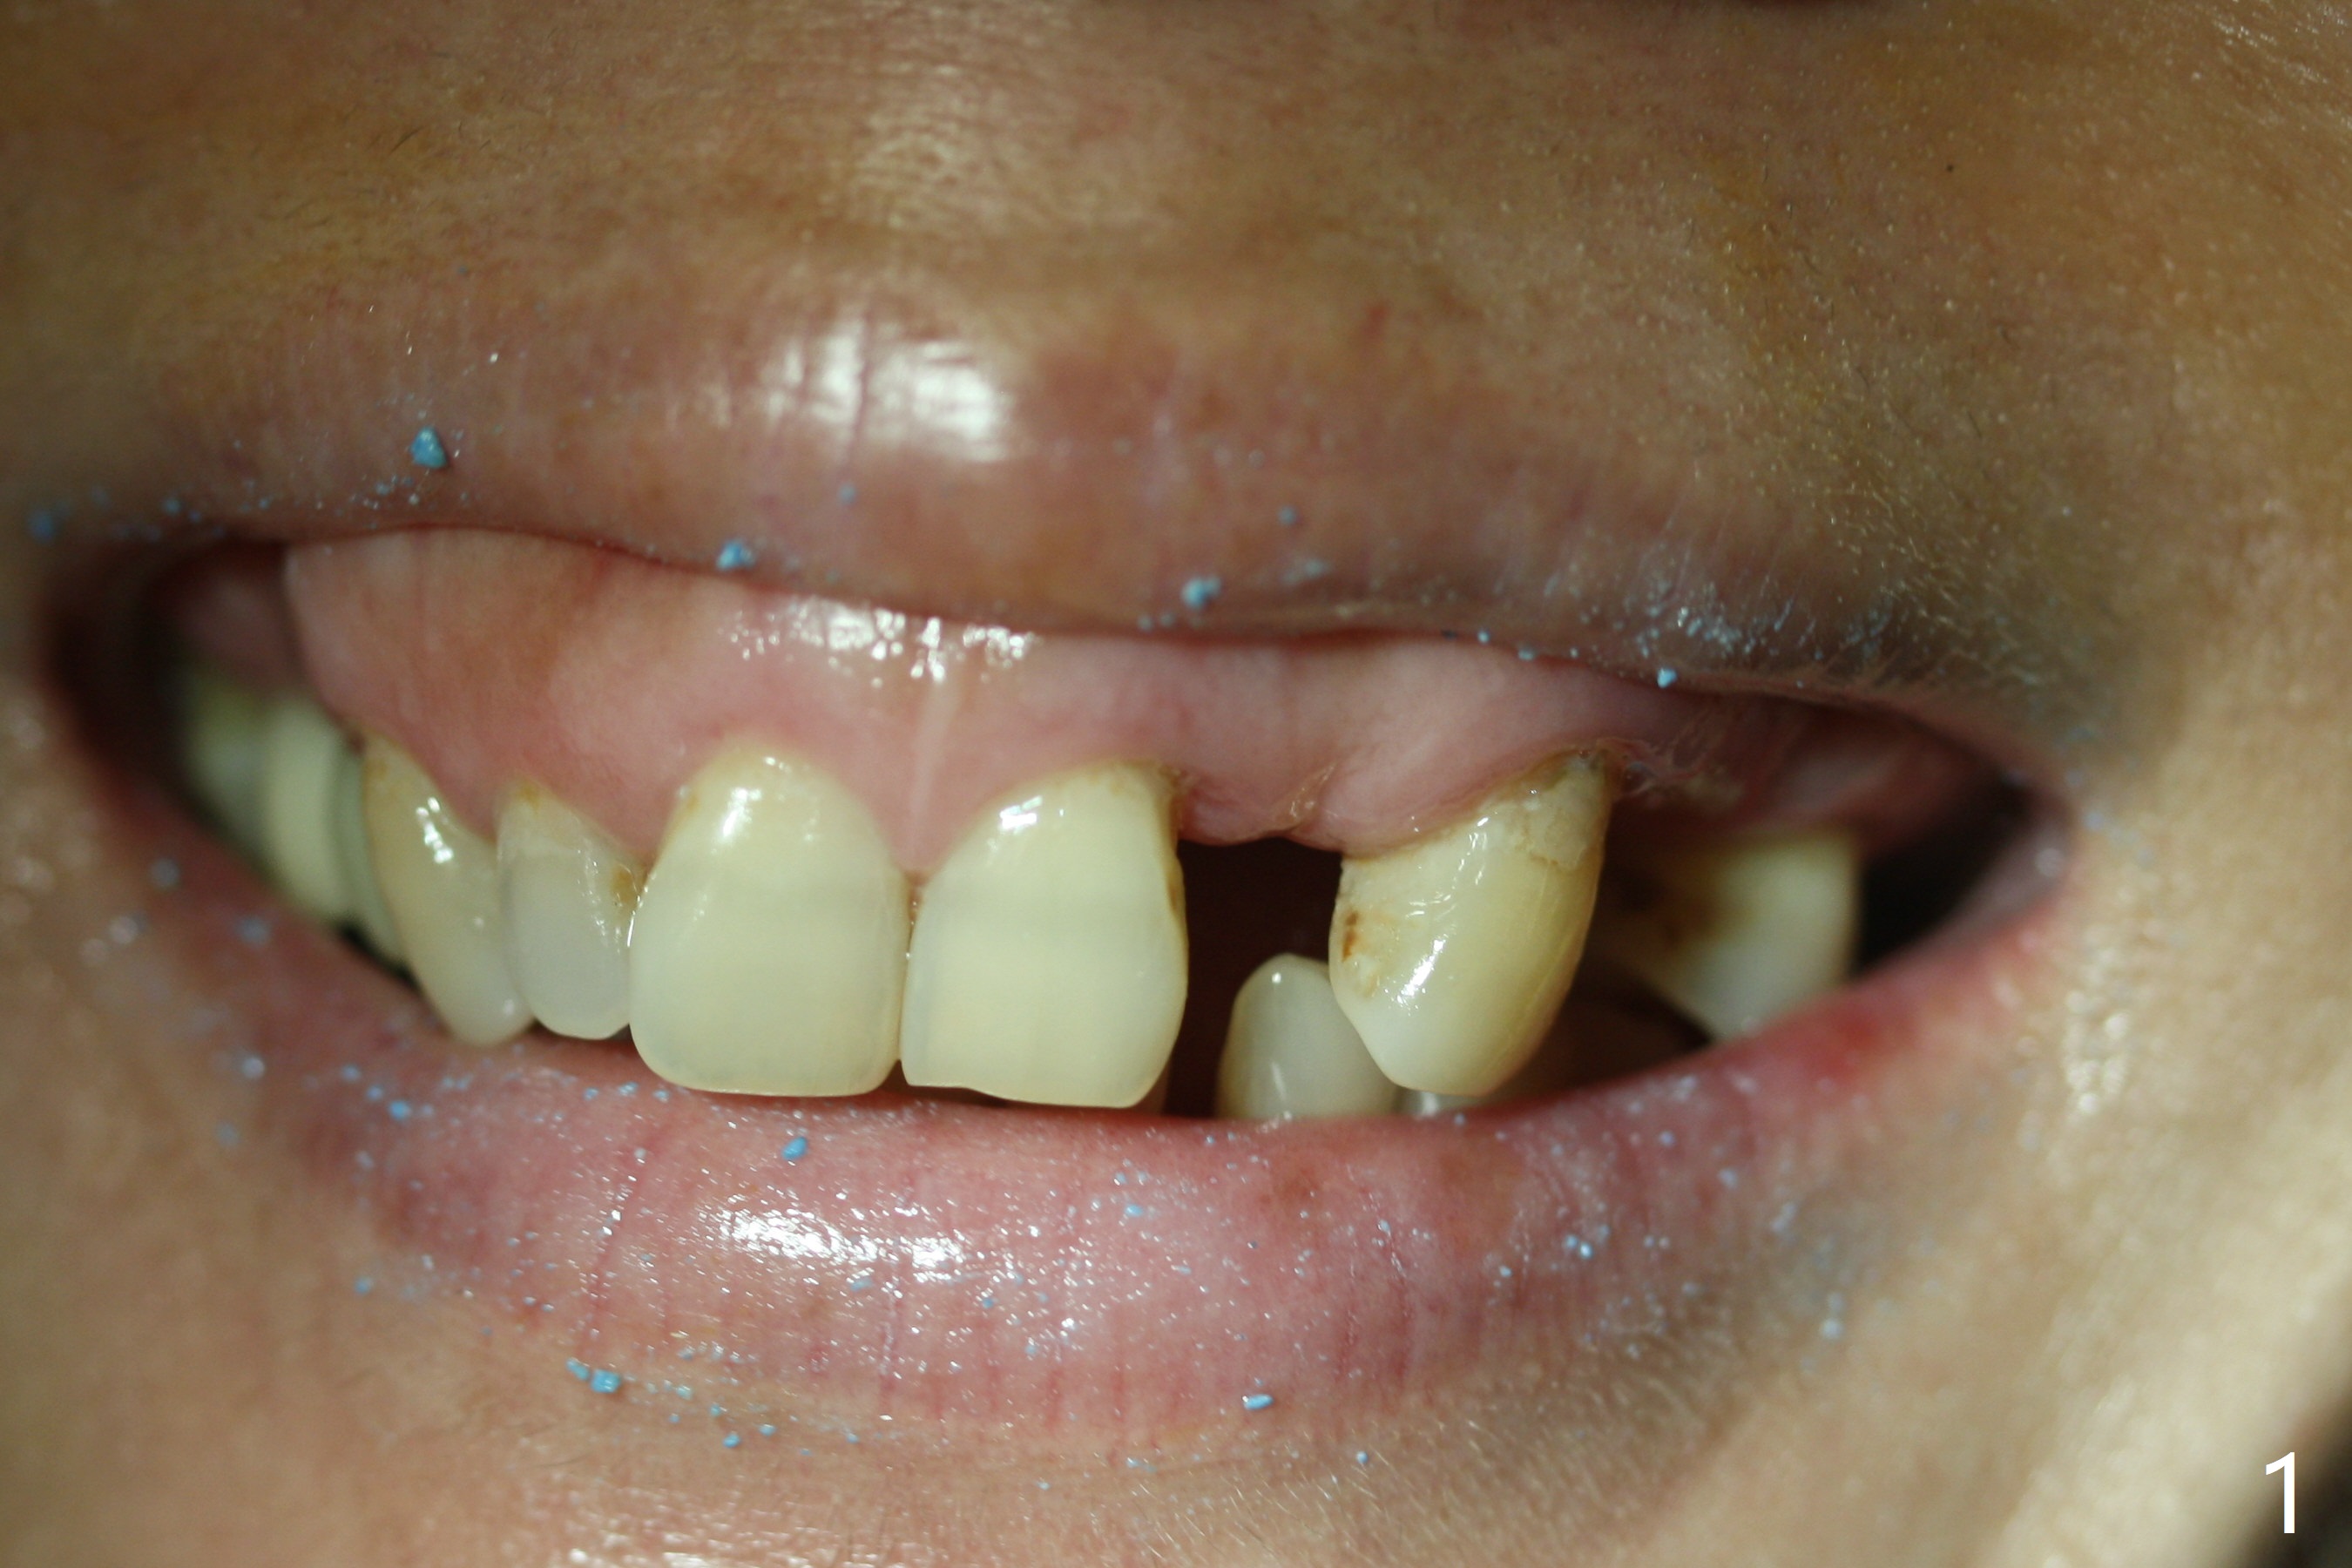

The patient has gummy smile (Fig.1).  The edentulous ridge at #10 has buccal concavity (Fig.2 *).  The surgical guide fits well without #9 distal trimming.  With 34 mg Xylocaine and 17 mcg Epinephrine infiltration at #10 and 12, the patient feels pain when 2.2 (in fact 1.9) x8.5 mm drill is being used.  When Septocaine is added, the osteotomy at #10 is found distal.  Out of curiosity, PA is taken with 2.2x10 mm drill in place; its trajectory seems satisfactory (Fig.3).  When a 2.5x13 mm 1-piece implant is placed free hand, it deviates palatal, which is confirmed with incision after addition of 34 mg Xylocaine and 34 mcg Epinephrine.  A new osteotomy is created by S-Mini Kit buccal to the previous one.  With Lindamann bur to adjust the position of the new osteotomy twice, the last drill (2.0 mm) apparently starts to perforate the apical portion of the buccal plate.  The perforation seems to enlarge when the mini implant is re-placed (Fig.4, 8 (green area) <30 Ncm).  With Vanilla graft (Fig.8 pink circles) and abutment height adjustment (Fig.4), a provisional is fabricated with occlusal clearance.  There are two reasons for failure of the surgical guide: failure to trim the tooth #9 distal (minor palatal guide displacement, Fig.5) and deflection of pointed drill and 2.2 mm drills over the hard palatal plate slope (Fig.6).  To avoid this complication, the pointed drill should be done free hand initially, after incision and obliquely (Fig.7).  The guide is placed to finish the rest of osteotomy if deem to be appropriate.